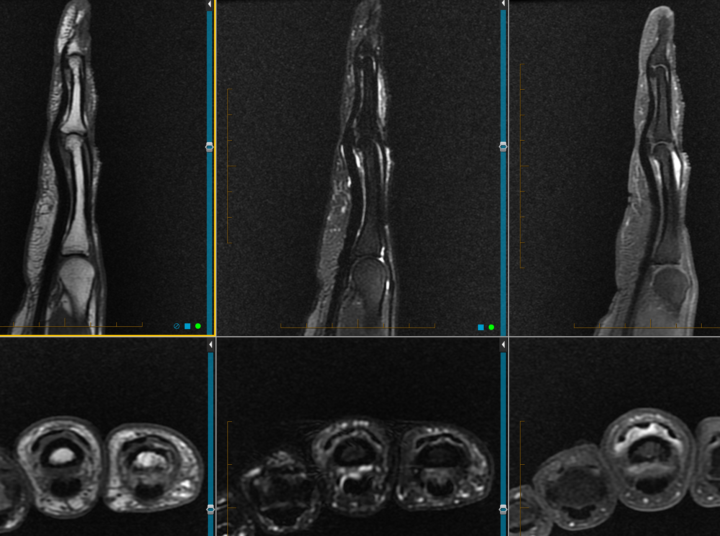

Need help with this finger case ( NORA ?)

30 Y O man Growing lump . I think about a NORA tumor as my first differential . Any other ideas.